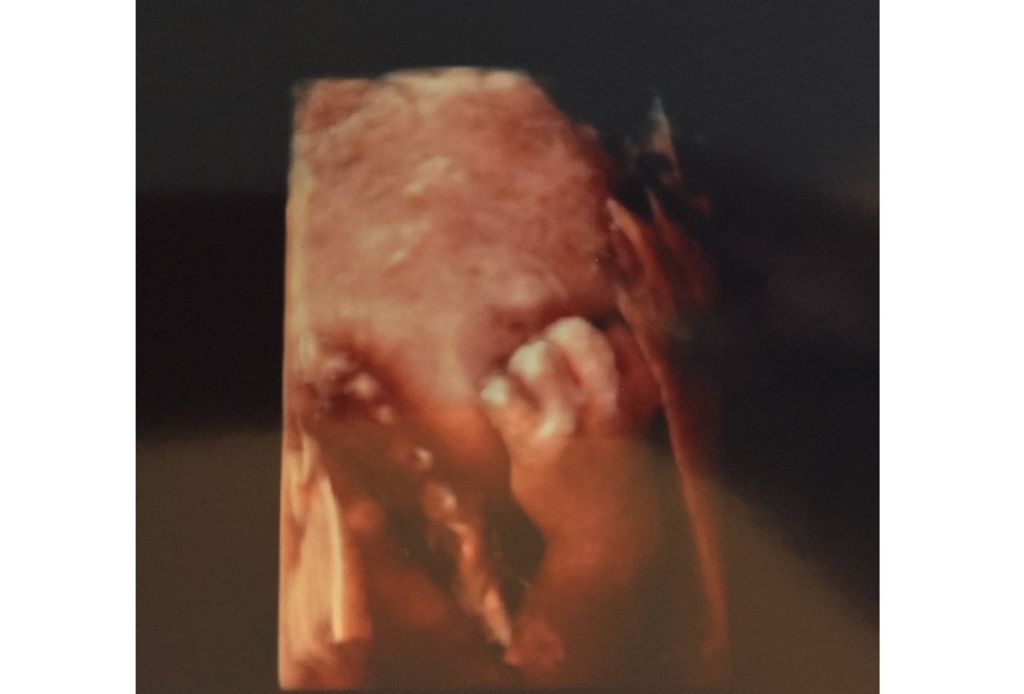

そんなあっくんはお顔を取られるのも嫌なようです.エコー検査のたびに3D写真で顔を撮影することを試みるのですが,どうもあっくんは顔を見せてくれません.両手両足を使って実に巧妙に顔を隠しているようなのです.

気付いているのか,たまたまなのか,いつもそうなのかは定かではありませんが,とにかく毎回絶妙にお顔を隠しているようです.こんな感じ↓

手!手!!!手がめっちゃきれいに映っているじゃないか!?